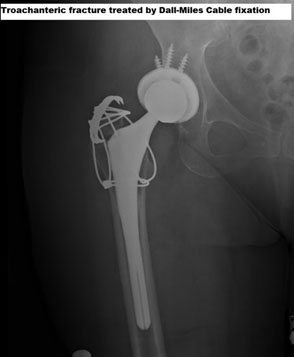

VANCOUVER TYPE A

A male patient who underwent THR 2 years ago comes with pain in the hip, and X-ray shows this trochanteric fracture. Fracture treated with surgical fixation of the trochanteric fracture.